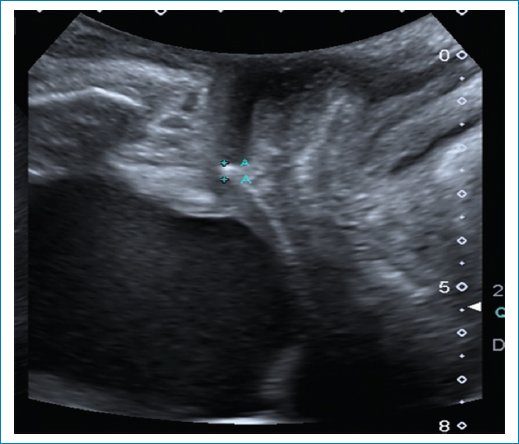

• – Cistocele: con el examen físico solamente podemos evaluar un prolapso de la pared anterior de la vagina; sin embargo, con las imágenes podemos diferenciar entre un cistouretrocele que se asocia a incontinencia de orina y un cistocele con ángulo retrovesical intacto con síntomas de obstrucción al vaciado y baja probabilidad de incontinencia de orina. También puede ser que el prolapso de la vagina anterior sea por un divertículo uretral, quiste de Gartner o un enterocele anterior. El punto de corte para determinar el descenso de la vejiga es 10 mm por debajo de la línea pubiana que se traza perpendicular a la sínfisis pubiana3 (Fig. 7).

Figura 7. Se observa un descenso de la pared posterior vesical por debajo de la línea pubiana, con ángulo retrovesical cerrado.